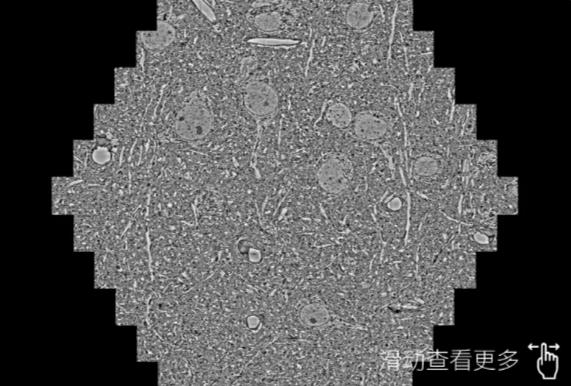

鼠脑切片。左图使用定西蔡司定西扫描电镜MultiSEM706对165μmx143pm面积区域成像,耗时仅需1.5秒。右图为鼠脑切片中30μm区域放大效果。样品由芝加哥大学B.Kasthuri提供。

使用蔡司高速定西扫描电镜MultiSEM对1mm²人脑皮层组织进行高分辨成像,并对其中的各种细胞结构进行三维重构分析。左图展示了2x3mm²组织平面中锥体神经元的三维重构效果。右图显示了局部体积神经元三维重构。图像由哈佛大学chtman实验室提供,渲染图由D. Berger 制作。